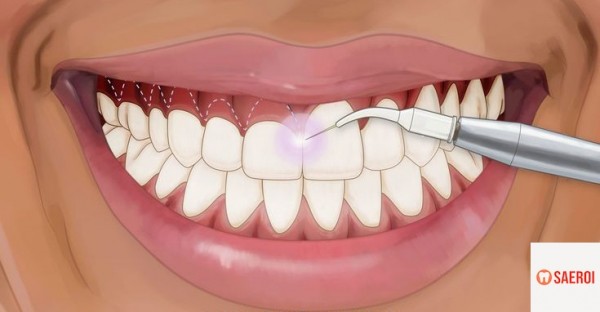

(1) 잇몸 절제술(gingivectomy)

과도하게 증식된 잇몸이 많이 보이는 경우

증식된 잇몸을 레이저 등을 이용하여 절제해 줄 수 있습니다.

짧아졌던 치관이 길어 보임과 동시에

미소 시 보이는 잇몸의 양도 줄어든 것을 볼 수 있습니다.

간혹 절제한 잇몸이 재증식 하는 경우가 있을 수 있습니다.